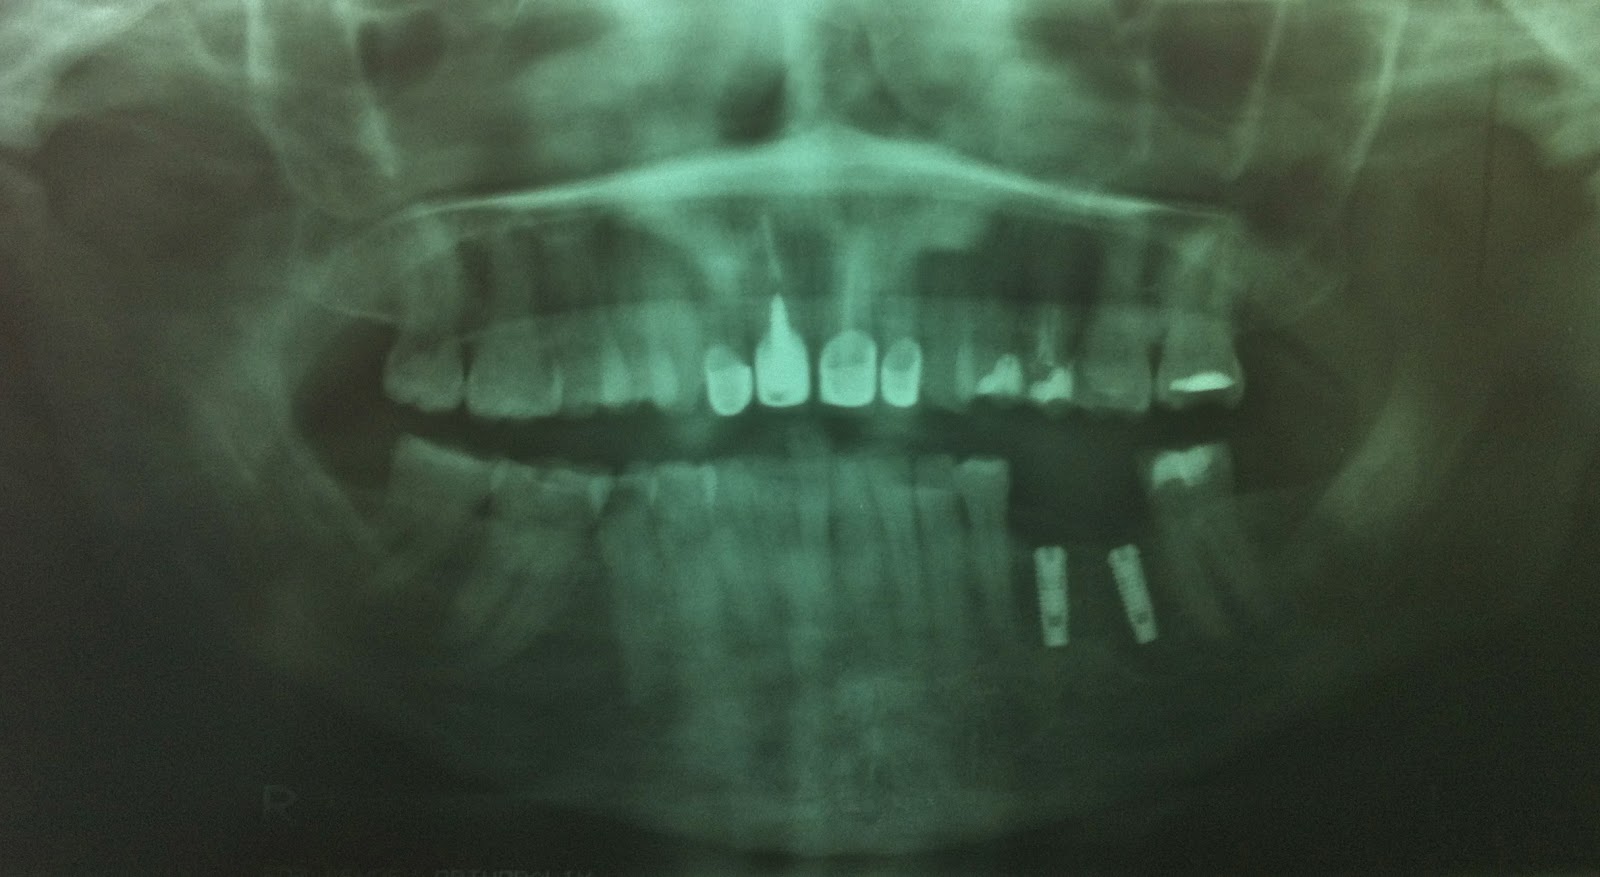

Dental XRay Panoramic of Upper and Lower Jaw.Dental Implant Pro Stock Healthy Dental Implant X Ray Normal radiographic findings around dental implants. They provide detailed insights into the oral anatomy, enabling dentists to. Use of periapical and bitewing radiographs is often adequate to assess the quality. Discover how they help dentists assess bone quality, plan implant. At the heart of successful dental implant procedures lies a meticulous planning process, and a cornerstone of this planning is. Healthy Dental Implant X Ray.

OPG Showing Implant Cases Brij Dental Clinic Healthy Dental Implant X Ray Discover how they help dentists assess bone quality, plan implant. At the heart of successful dental implant procedures lies a meticulous planning process, and a cornerstone of this planning is the utilization of dental implant x. Use of periapical and bitewing radiographs is often adequate to assess the quality. Normal radiographic findings around dental implants. They provide detailed insights into. Healthy Dental Implant X Ray.

(A) Panoramic Xray shows 4 dental implants placed in the native and Healthy Dental Implant X Ray Normal radiographic findings around dental implants. Use of periapical and bitewing radiographs is often adequate to assess the quality. They provide detailed insights into the oral anatomy, enabling dentists to. Discover how they help dentists assess bone quality, plan implant. At the heart of successful dental implant procedures lies a meticulous planning process, and a cornerstone of this planning is. Healthy Dental Implant X Ray.